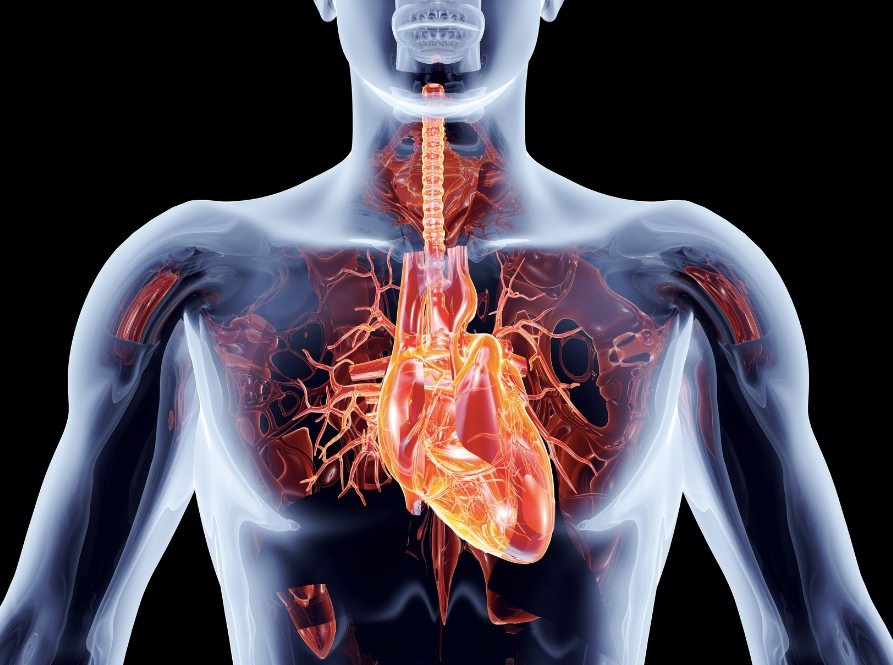

The truth is that heart disease kills the most people. One of the main causes of heart attack and stroke is clogged arteries, which can interrupt blood flow throughout the body.

There are many factors that can increase the risk of a heart attack, such as lack of exercise, stress and an unhealthy diet.